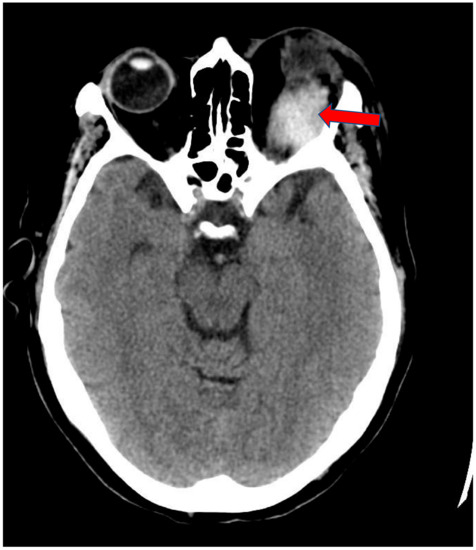

2. Case Presentation